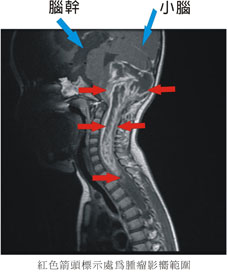

終日愁眉不展以淚洗面的父母,再度到第三家醫學中心求診,得到的答案與第二家相同,仍建議以手術切除,雖無多大把握但至少比將來腫瘤持續擴大威脅生命要多一線生機。邱小弟父母及長輩們皆不贊成年幼的孩童接受沒有把握且高風險的手術治療,因此嘗試以中藥來緩和症狀,但病情仍逐漸惡化, 在邱小弟一歲十個月時,父母親抱著幾乎一歲十個月大但卻四肢全癱及煩躁不適的邱小弟至本院求診,腦部磁振造影檢查後發現腫瘤不斷擴大,並向下侵犯至第四胸椎之脊髓(圖一),小腦及腦幹嚴重受壓、腦室擴大(水腦)在決定留在本院治療後,於2009年3月20日至5月20日,總共接受28次導航螺旋刀放射線治療(圖二)。

紅色箭頭標示處為腫瘤影響範圍